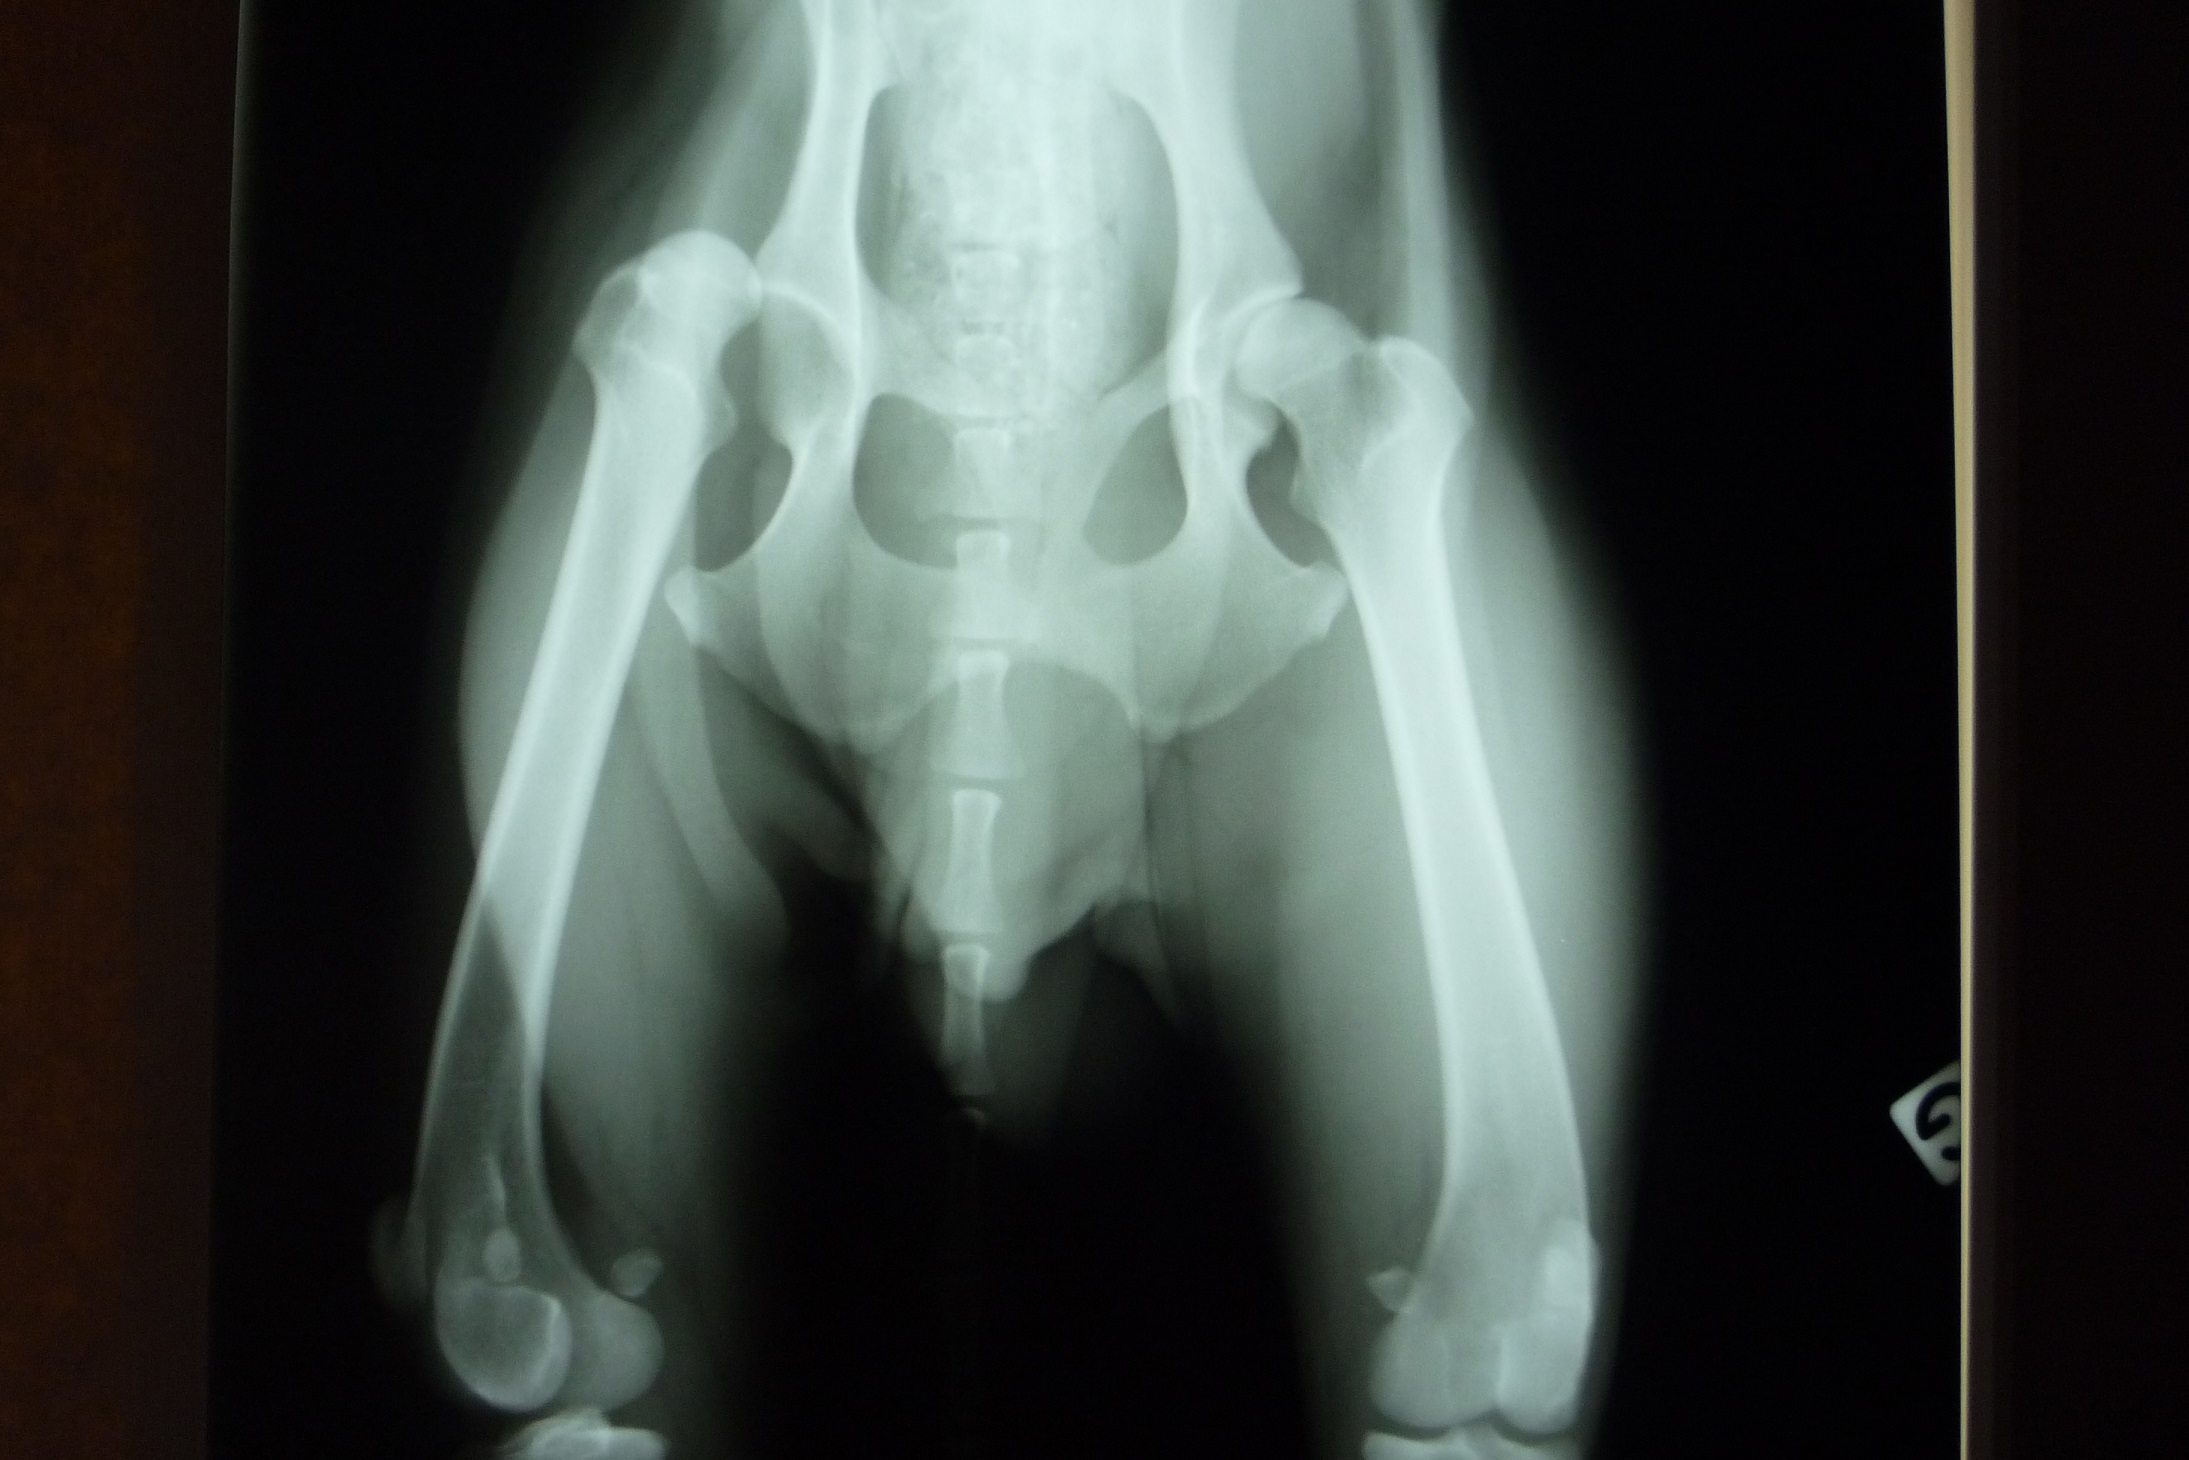

Notre bénévole a donc récupéré le pauvre loulou, consultation vétérinaire, radio : luxation de la tête du col du fémur mais comme souvent dans ces cas-là, la manipulation n’est plus suffisante car la luxation est trop ancienne, la chirurgie est indispensable (résection de la tête du fémur).